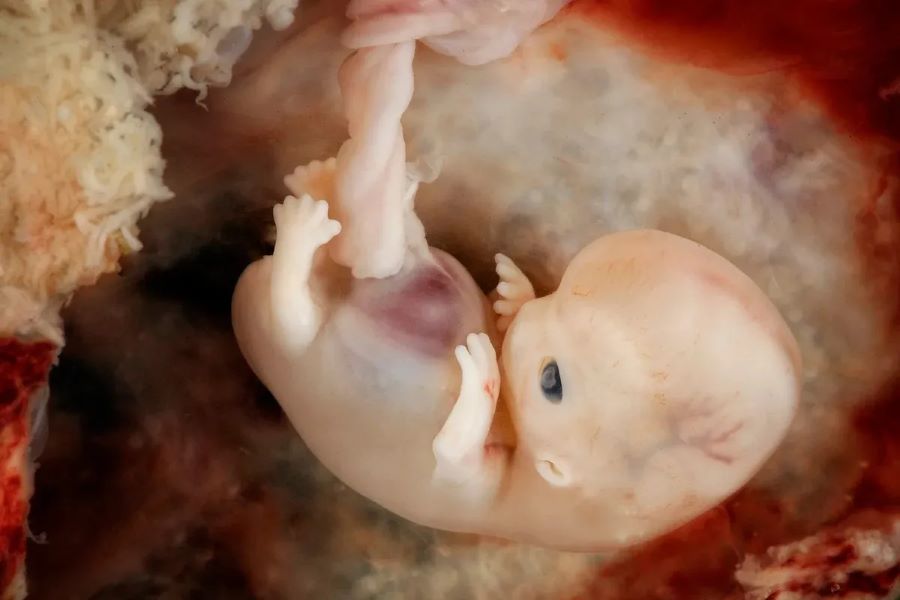

تطورات الجنين في الأسبوع 12 من الحمل

يستمر الجهاز العصبي بالكامل في النمو، ويبدأ ظهور الأعضاء التناسلية بشكل غير واضح، يبدأ الجسم في إنتاج خلايا الدم الحمراء والبيضاء ويبدأ جهاز المناعة في العمل، وينشط الكبد والطحال بشكل أكبر، تبدأ أيضاً كلاً من الغدد اللعابية والغدد العرقية في العمل وإفراز اللعاب والعرق بالإضافة إلى ظهور شعر الجسم.